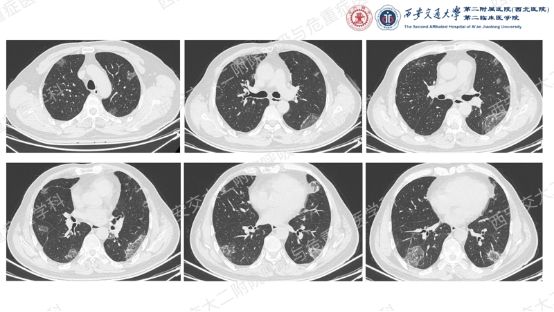

让我们一起从影像入手,看看这名患者的胸部CT特征:双肺多发斑片、实变和磨玻璃影,胸膜下和支气管血管束周围分布为主,病灶无明显空洞、钙化,可见散在支气管充气征,反晕征(中心磨玻璃影 + 外周环形实变影)尤为显著,伴典型“环礁征”(病灶边缘呈结节状隆起,类似环礁形态)。基于这些特征性影像学表现,同时排除细菌、真菌、结核感染及结缔组织病、肿瘤等常见病因,临床诊断隐源性机化性肺炎(COP)。

本例患者虽未获得典型的病理确诊依据,但结合其“双肺多发胸膜下病灶、反晕征+环礁征”的特征性影像学表现、抗感染治疗无效的临床经过,以及全面排除感染、肿瘤、结缔组织病等其他病因,临床诊断COP的依据已充分。

该患者确诊后,按体重给予50mg(0.75mg/kg)强的松晨起顿服,1月后复查胸部CT提示肺部阴影吸收好转,随后调整剂量为40mg/d,之后以 “每月顿服量减1片”的速度逐步减量,减至10mg/d维持3月,又减至5mg/d维持3月,总疗程13个月。治疗期间定期监测血压、血糖、电解质,未出现明显激素相关不良反应;最终复查胸部影像学示病灶基本吸收